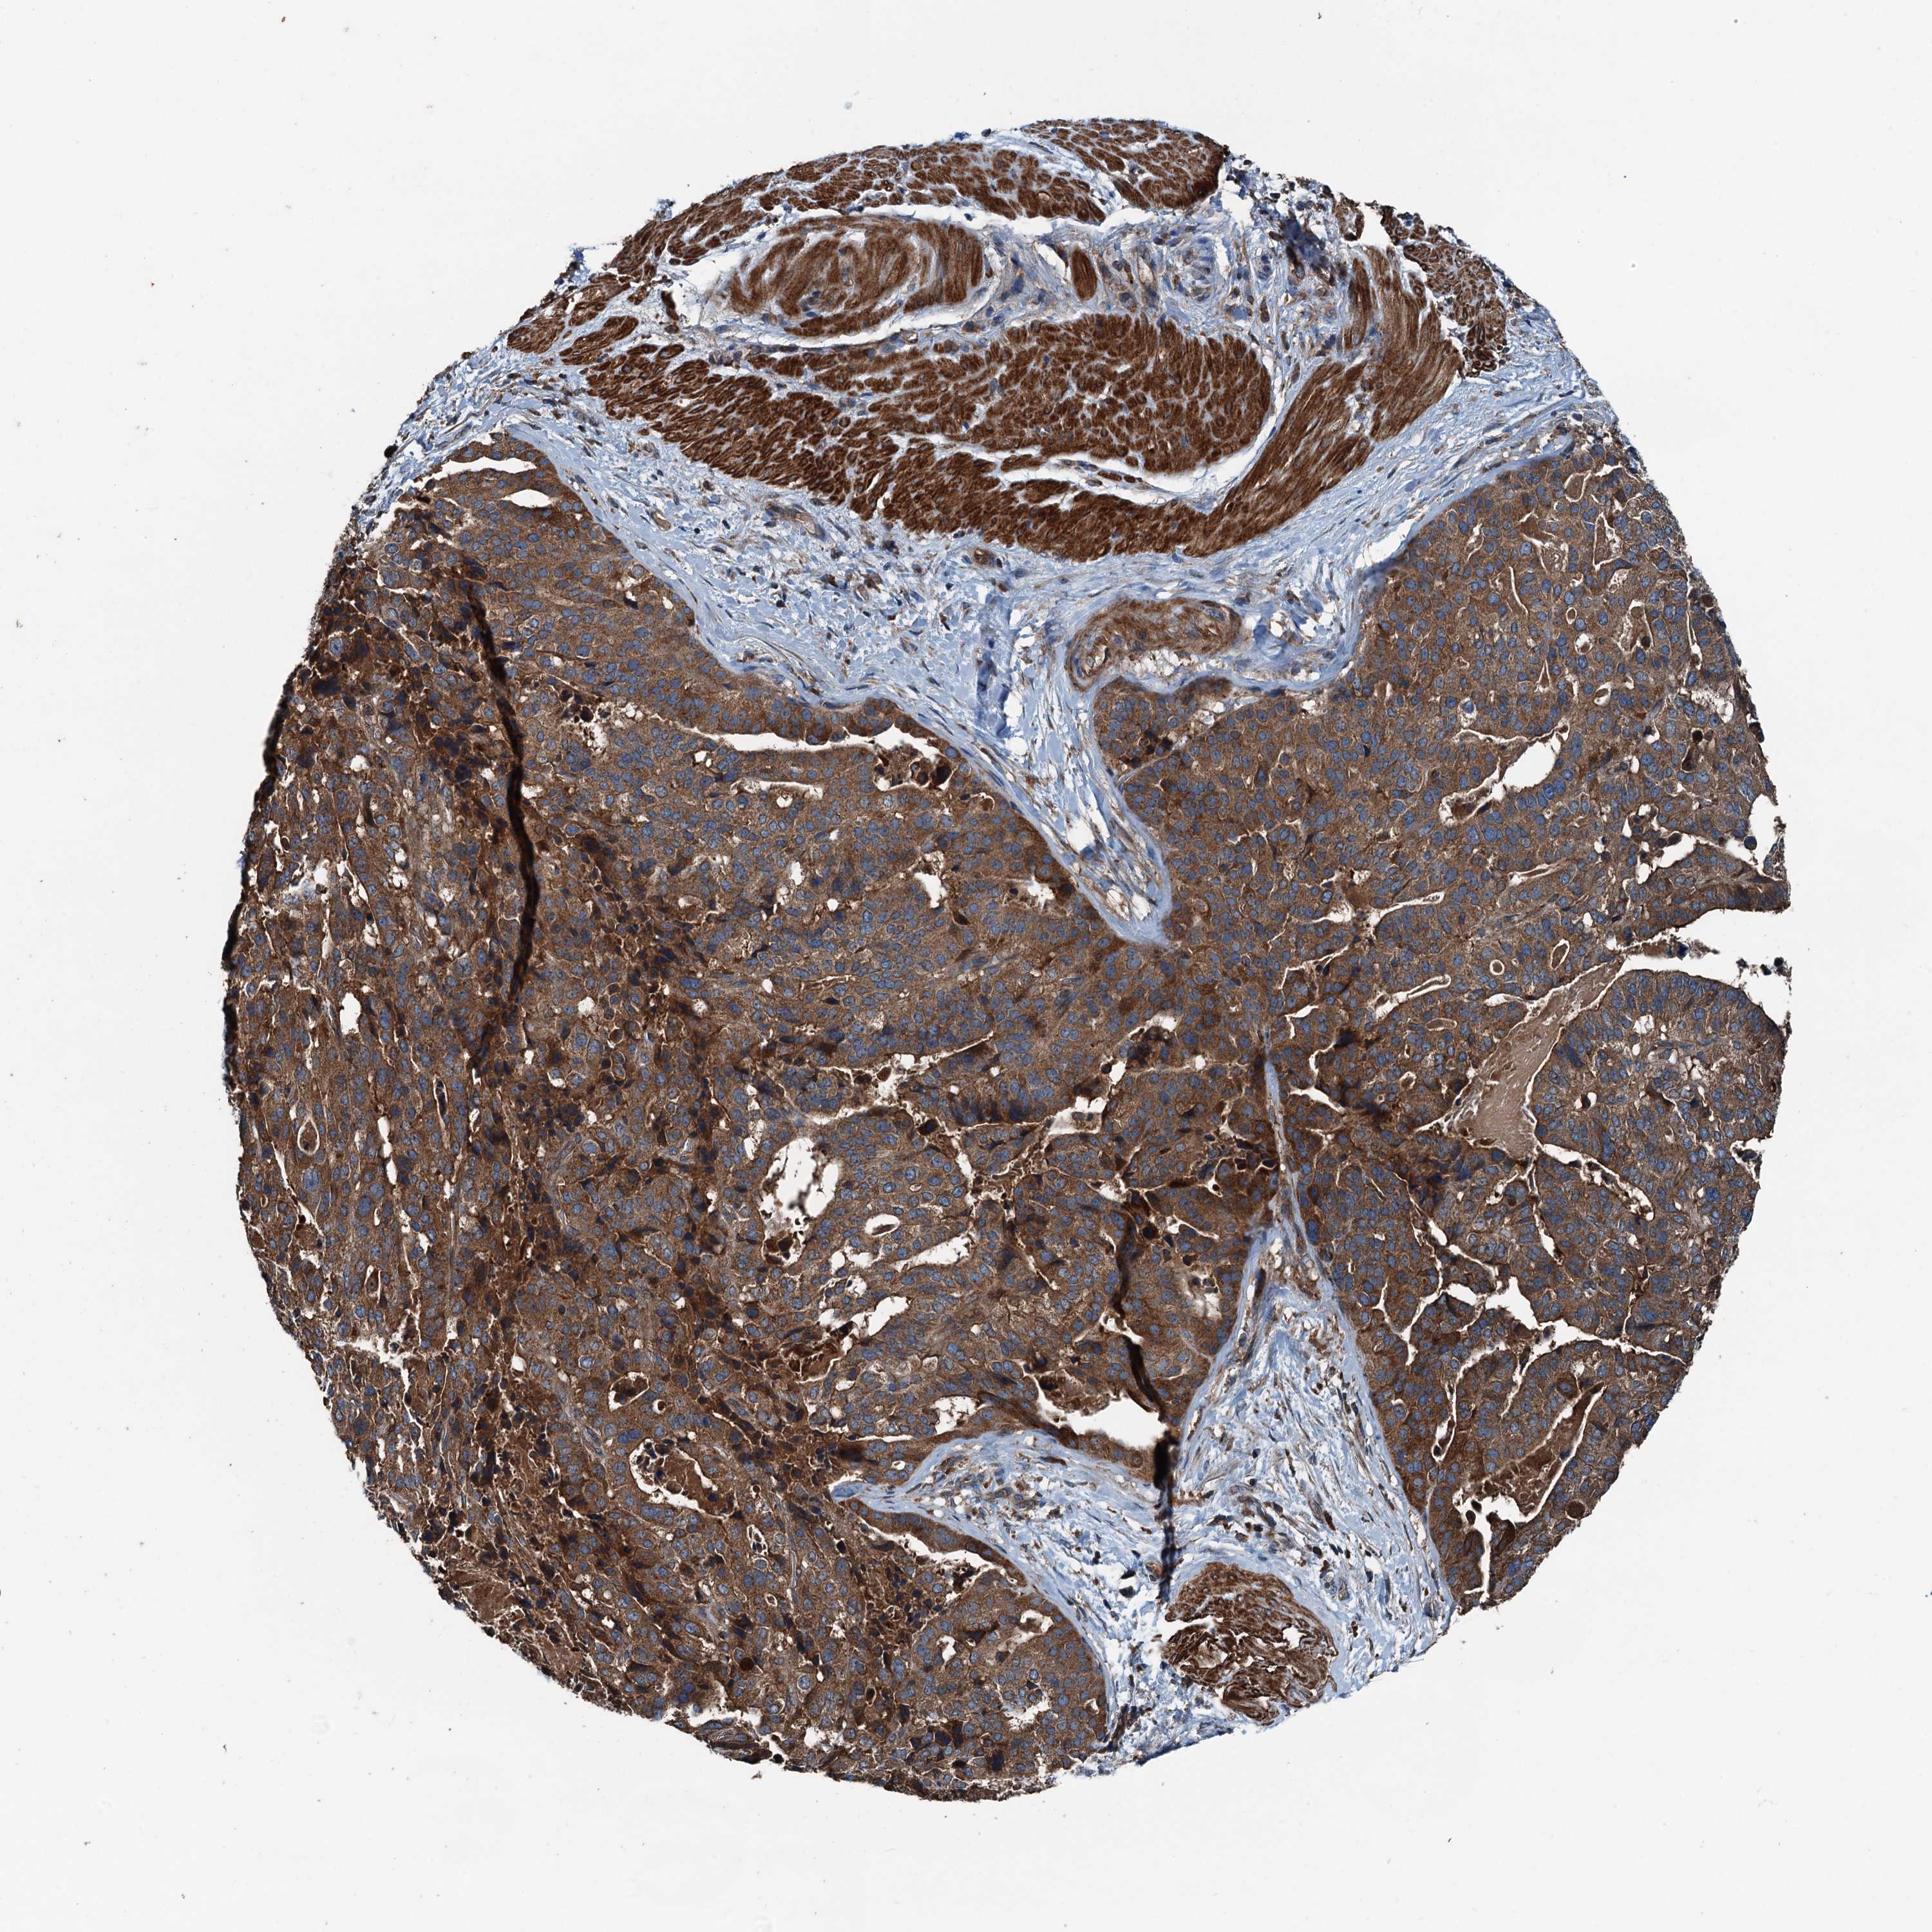

STOMACH CANCER - Protein expressioni

A mouse-over function shows sample information and annotation data. Click on an image to view it in a full screen mode. Samples can be filtered based on level of antibody staining by selecting one or several of the following categories: high, medium, low and not detected. The assay and annotation is described here.

Note that samples used for immunohistochemistry by the Human Protein Atlas do not correspond to samples in the TCGA dataset.

Antibody stainingi

Antibody staining in the annotated cell types in the current human tissue is reported as not detected, low, medium, or high, based on conventional immunohistochemistry profiling in selected tissues. This score is based on the combination of the staining intensity and fraction of stained cells.

Each image is clickable and will lead to virtual microscopy that enables deeper exploration of all samples and also displays staining intensity scores, fraction scores and subcellular localization as well as patient and tissue information for each sample.

Antibody HPA041227

Staining

High

Medium

Low

Not detected

Intensity

Strong

Moderate

Weak

Negative

Quantity

>75%

75%-25%

<25%

None

Location

Nuclear

Cytoplasmic/membranous

Cytoplasmic/membranous,nuclear

Adenocarcinoma, NOS

Adenocarcinoma, High grade